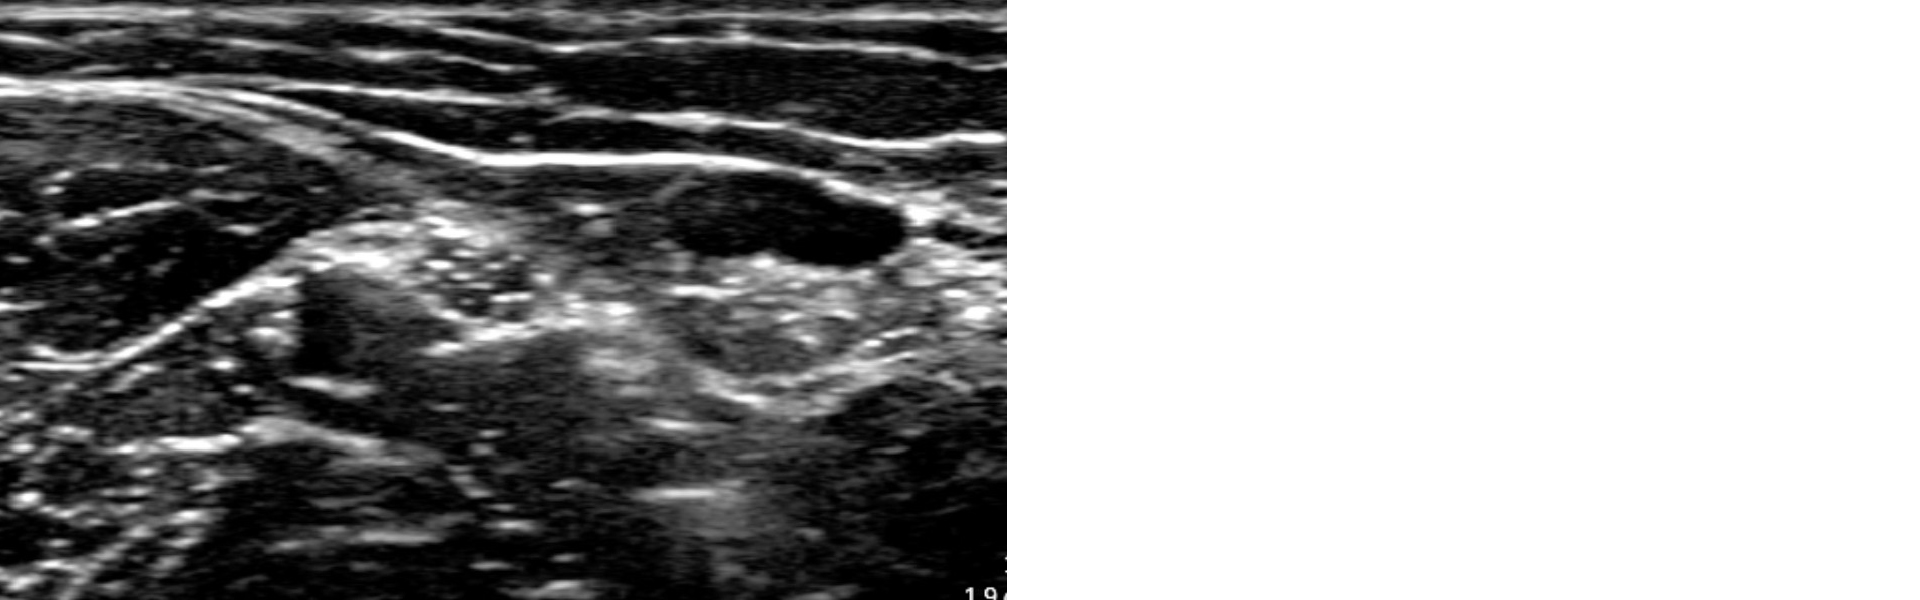

Figure 2

Ultrasound image of the median nerve superior to the elbow crease in the upper limb obtained using the handheld ultrasound device GE Vscan AIR™ CL

Ultrasound image of the median nerve superior to the elbow crease in the upper limb